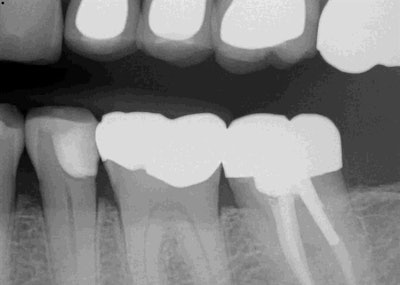

A 70-year-old man presented with a failing direct composite on tooth #20 with recurrent caries on the gingival margin. This tooth also presented as a "food trap" issue for the patient. Upon clinical and radiographic examination, it became apparent that the gingival margin was not restored properly on the existing distal-occlusal lingual (DOL), which led largely to the failure of the composite.

The preparation was quite wide and extended slightly subgingival near the lingual portion of the preparation. The wide box, curving tooth, and subgingival extension of the preparation add to the complexity of predictably restoring these types of cases.

Surefil SDR (Dentsply Sirona) was then placed in the gingival 1-1.5 mm of the proximal box and cured, followed by three layers of Filtek Supreme (3M). Finally, the restoration was polished using a Meisinger polishing kit. Postop radiographs confirm the gingival margin.